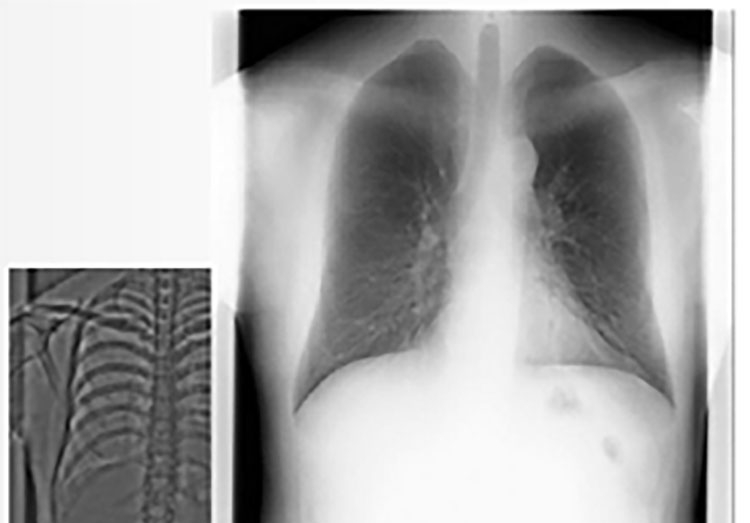

2009年より約15年間使用していた胸部X線撮影装置をこの度、最新鋭の装置にリニューアルいたしました。 この装置は診断能向上に貢献するアプリケーション、円滑な撮影を実現するきめ細やかな設計、高画質・低線量を追求した画像処理機能に“診やすく”、そして受診者様に“やさしい”次世代のX線撮影装置となっています。 ①2ショット法エネルギーサブトラクション機能 2ショット法エネルギーサブトラクションとは、骨と軟部組織のX線吸収差を利用し、収集画像に最適な係数を掛けて差分(サブトラクション)することで、単純X線写真に加えて軟部(骨除去)画像と骨

②モーションアーチファクト抑制機能 一般的なモーションアーチファクトとは、撮影中に体が動くことで、画像がブレて見づらくなる現象です。胸部X線検査では、息止め不良や心拍によりブレが発生し、画像上で骨と軟部の境界線がボヤけてしまいますが、この機能によりアーチファクトが大幅に低減されます。③検査指示をわかりやすく伝える検査支援システム 「音声」による指示だけでなく、カラー液晶モニタを搭載することにより、「文字」と「画像」も合わせて表示し、より的確・直感的に受診者様へ伝えるとともに、聴覚が弱い方、もしくはまったく聞こえない方にも、検査指示が可能となりました。 また、日本語が理解できない外国の方の